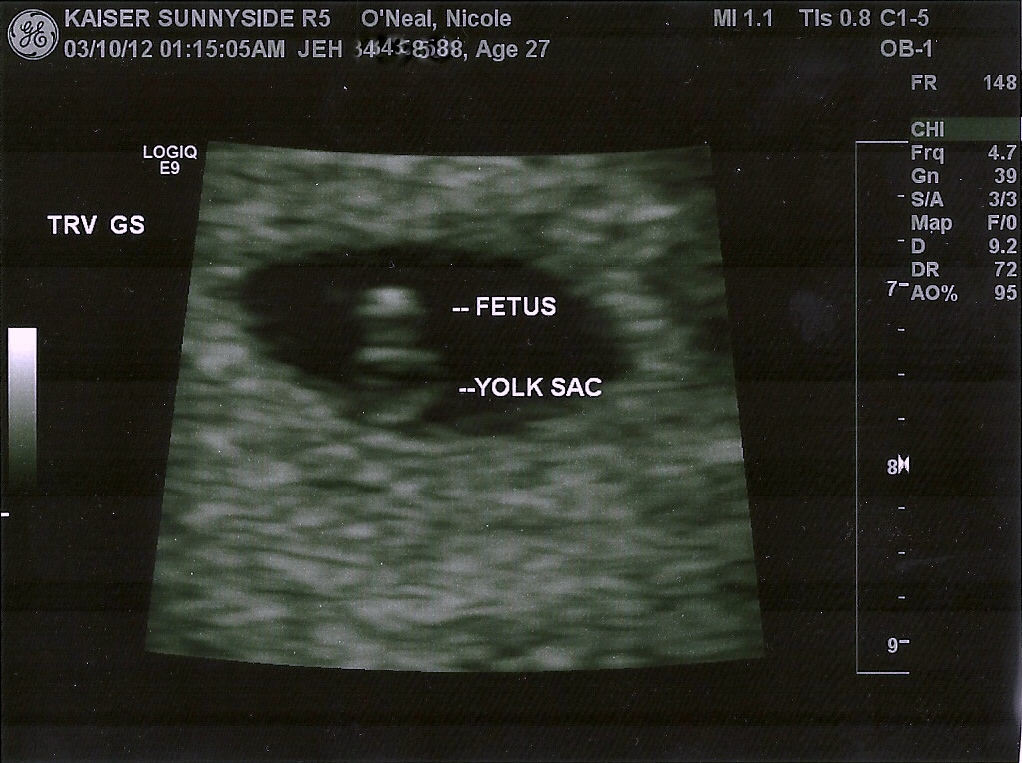

We watched as he moved the wand around…said, this is your

Sac, and this is where we will zone in to see if the fetus is viable….10

seconds later, he focused in a two blobs, and inside one of them…this crazy,

fast, twitching thing…HEART BEAT! 116 beats a minute, which he wants to be over

90 at this stage.

So we had our first ultrasound and got our first picture…